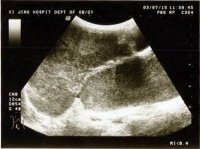

(一)B超:可明确肿瘤的大小形态囊实性部位及与周围脏器的关系鉴别巨大卵巢囊肿及腹水